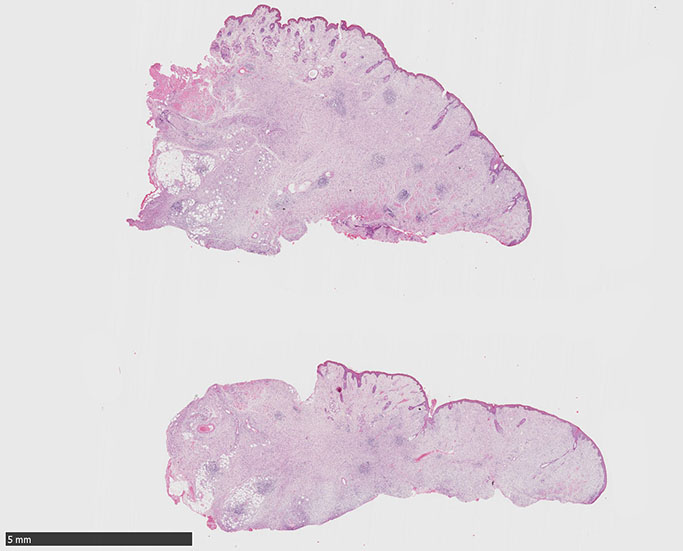

SPS244-Case02 項部皮下腫瘤 70歳代女性

潰瘍びらんはない割面loupe像